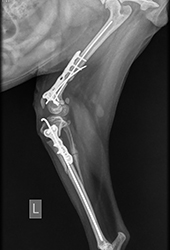

Beschwerden: Patellaluxation beidseits Grad 4, linke Hüfte subluxiert, Femurverkrümmung, Tibiarotation

Therapie: Operation linkes Bein, anschliessend Physiotherapie für rechtes Bein

Susi wurde in einer Tierklink genau untersucht, um die Grösse des Schadens festzustellen. Allein das Ergebnis der Röntgenuntersuchung ist für Susi katastrophal. Die linke Hüfte ist fast ausgerenkt (subluxiert) und beide Kniescheiben haben sich völlig vom Kniegelenk gelöst (Schweregrad 3-4). Der Oberschenkel ist verkrümmt und der Unterschenkelknochen hat sich verdreht. Durch die lange Schonhaltung ist die Muskulatur sehr schwach ausgebildet. Dazu ist eine genaue Beurteilung des Beckens und der Hinterbeine via CT notwendig. Das linke Hinterbein wurde operiert. Das rechte Hinterbein wird nur mit Physiotherapie behandelt.